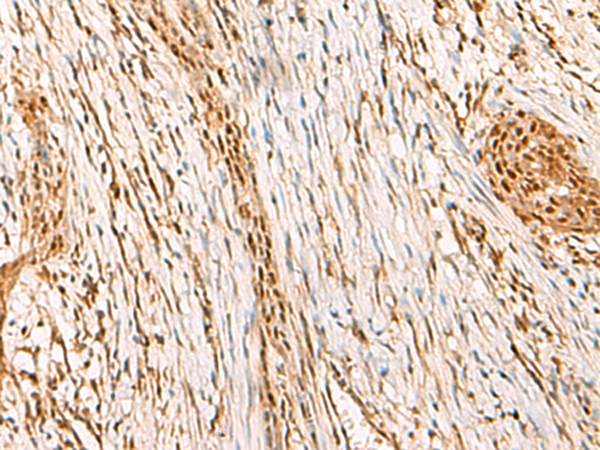

分类: 科研抗体货号: P03069别名: MLS; CCHL; MCOPS7; LSDMCA1应用: WB,IHC反应种属: Human, Mouse